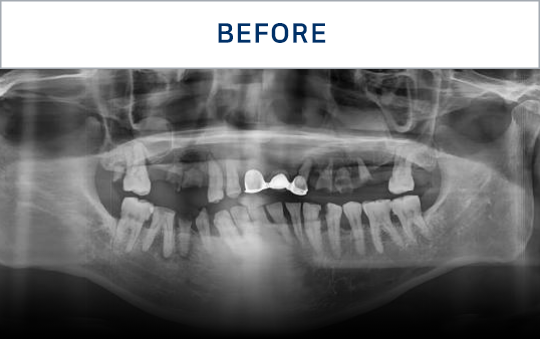

准确掌握口腔状况

了解所需的治疗方向

通过CT, 扫描等数字设

备拍摄后,

进行精密分析

考虑骨骼状态与神经位置,

制定种植位置与手术计划